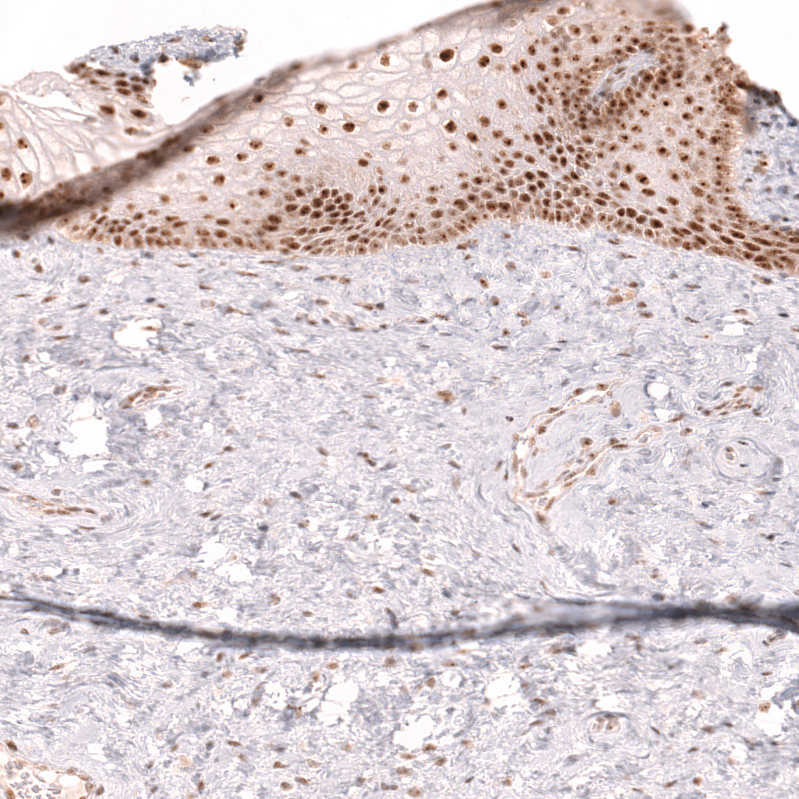

Immunohistochemistry analysis in human tonsil and liver tissues using AMAb91946 antibody. Corresponding TFEB RNA-seq data are presented for the same tissues.